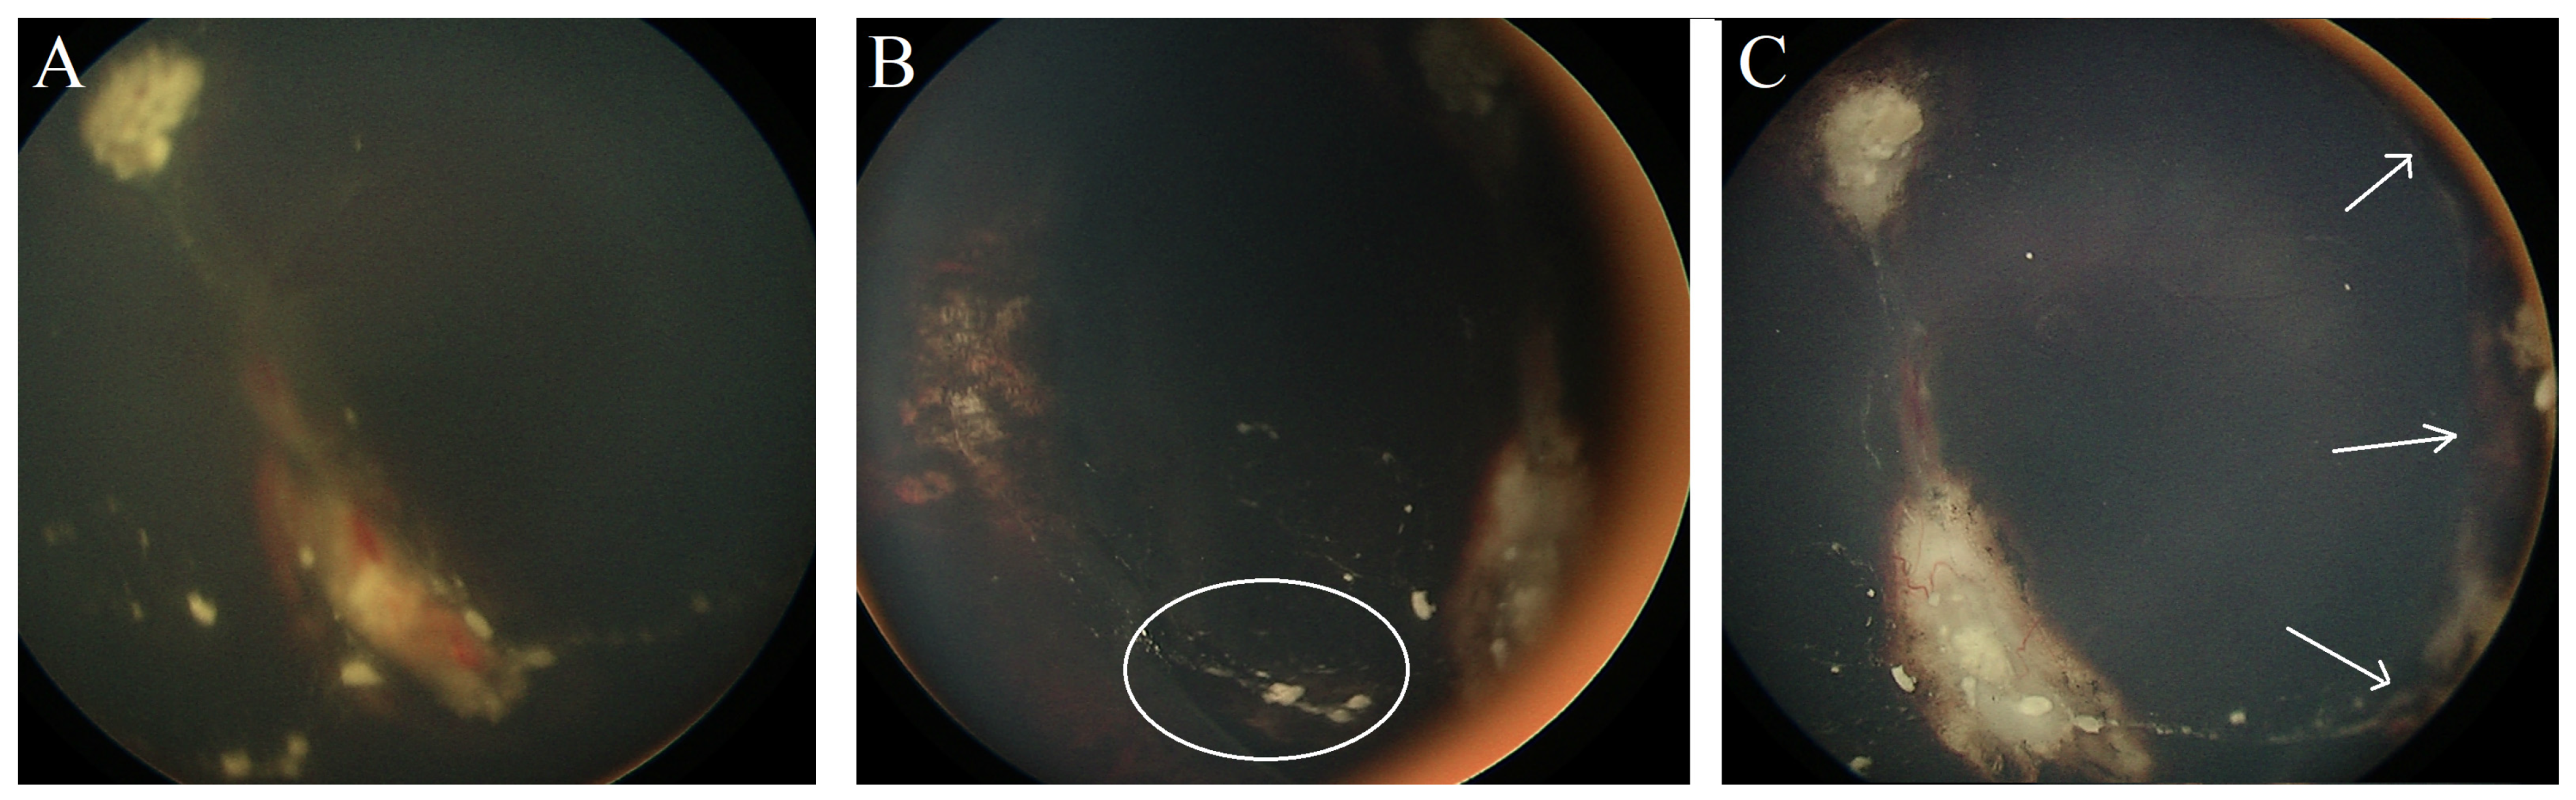

Case #4: A 12-month-old male patient had bilateral Rb (right eye group D, left eye group C). He was given six cycles of systemic chemotherapy (CVE) coupled with focal consolidation therapy (laser and cryotherapy). In addition, he received intravitreal Melphalan injections for active vitreous seeds in the left eye. Three months after the initial presentation, he developed RRD in the left eye (

Figure 3A), and a retinal break was found adjacent to the cryotherapy scar. Surgical retinal detachment repair was performed using a buckle without the need for fluid drainage, resulting in retina reattachment within four weeks (

Figure 3B). After 18 months of follow-ups, the patient maintained a reattached retina with an inactive calcified tumor and inactive vitreous seeds (

Figure 3C).